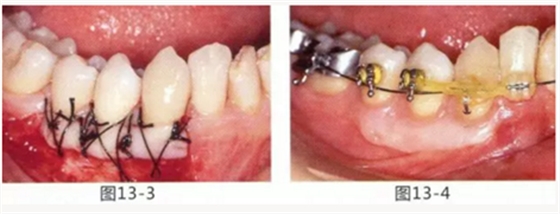

病例5

為了提高對修復(fù)體的術(shù)后效果,以生物學(xué)寬度,獲取附著齦為目的進行游離齦移植的病例

圖14-1 修復(fù)體周圍角化牙齦較少,很難進行清潔的狀態(tài),并有緣下齲壞的發(fā)生。

圖14-2,3 徹底去除齲壞后,試圖通過游離齦移植獲取生物學(xué)寬度和附著齦。

圖14-4~6修復(fù)體周圍角化牙齦較少,很難進行清潔的狀態(tài),并有緣下齲壞的發(fā)生。

圖14-7 配戴最終修復(fù)體完成5年后的狀態(tài)。保持良好。